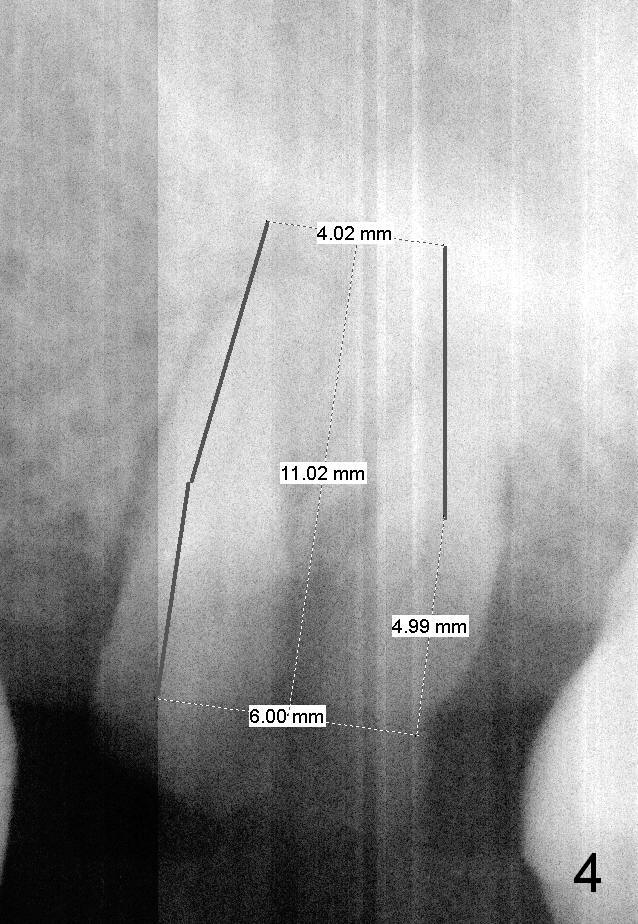

A 49-year-old man requests to restore #14 with residual roots (Fig.1). There is periapical radiolucency (Fig.2 *). A 5.9x10 mm bone-level implant is placed with minor sinus lift (Fig.3), whereas a short (Fig.4) or long (Fig.5) tissue-level implant is placed without or with sinus lift. The implant could be as large as 7 mm (Fig.5) to prevent post-extraction ridge atrophy.

To place an implant in the center of the septum, the smallest pilot drill will be used for 6 mm. Insert a parallel pin with millimeter marks and take the 1st intraop PA. Change the trajectory if necessary. Combination of reamers and osteotomes will be used to enlarge the osteotomy, followed by taps and an implant.